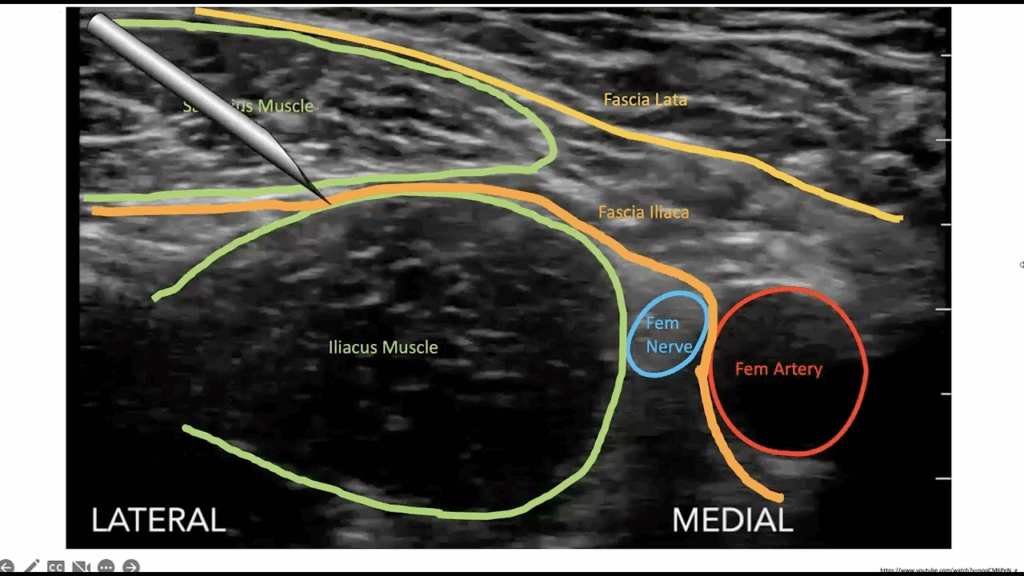

Bequer/Baker; US

Fascia Iliaca Block

Blocks femoral/obturator/lateral cutaneous nerves

Indications

•  femoral head/neck/trochanter fractures

• Anterior thigh lac/abscess

Careful on anticoagulated pts

Ropivicaine/bupivicaine preferred (longer acting)

Use linear probe

2 person procedure

• X2 syringe

• Threeway stopcock

Enter laterally between fascial planes